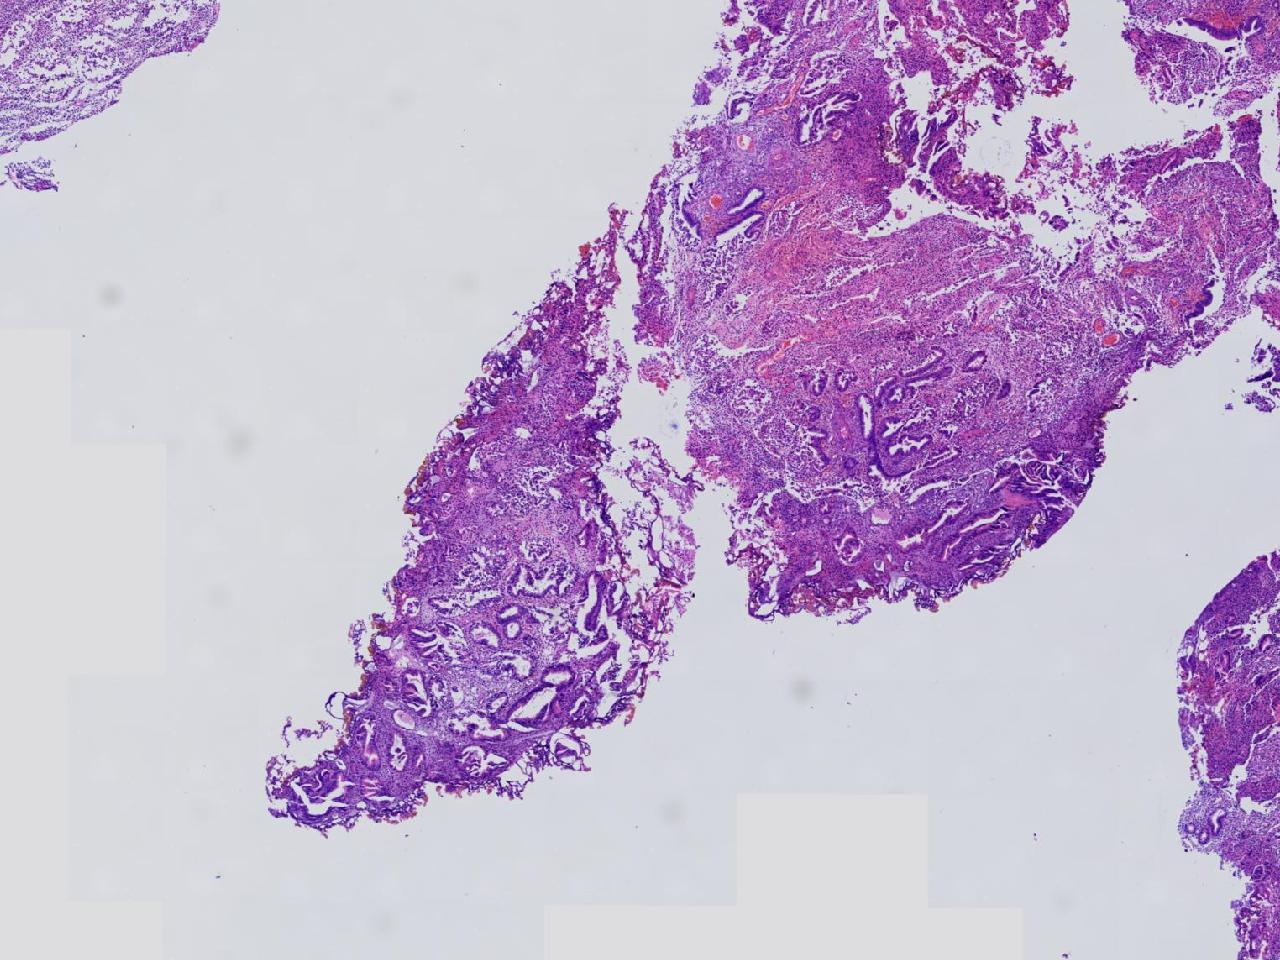

请教。1.有没有非典? 2.内膜是什么变化?

女,50岁,彩超示:粘膜厚度1.1cm。宫腔可见数个高回声,提示宫腔息肉。

子宫内膜+内膜息肉

灰粉色不整形软组织多块,3X3X2厘米。

子宫内膜息肉。

没有非典。

无非典型性子宫内膜增生,子宫内膜息肉

无非典内膜伴息肉。